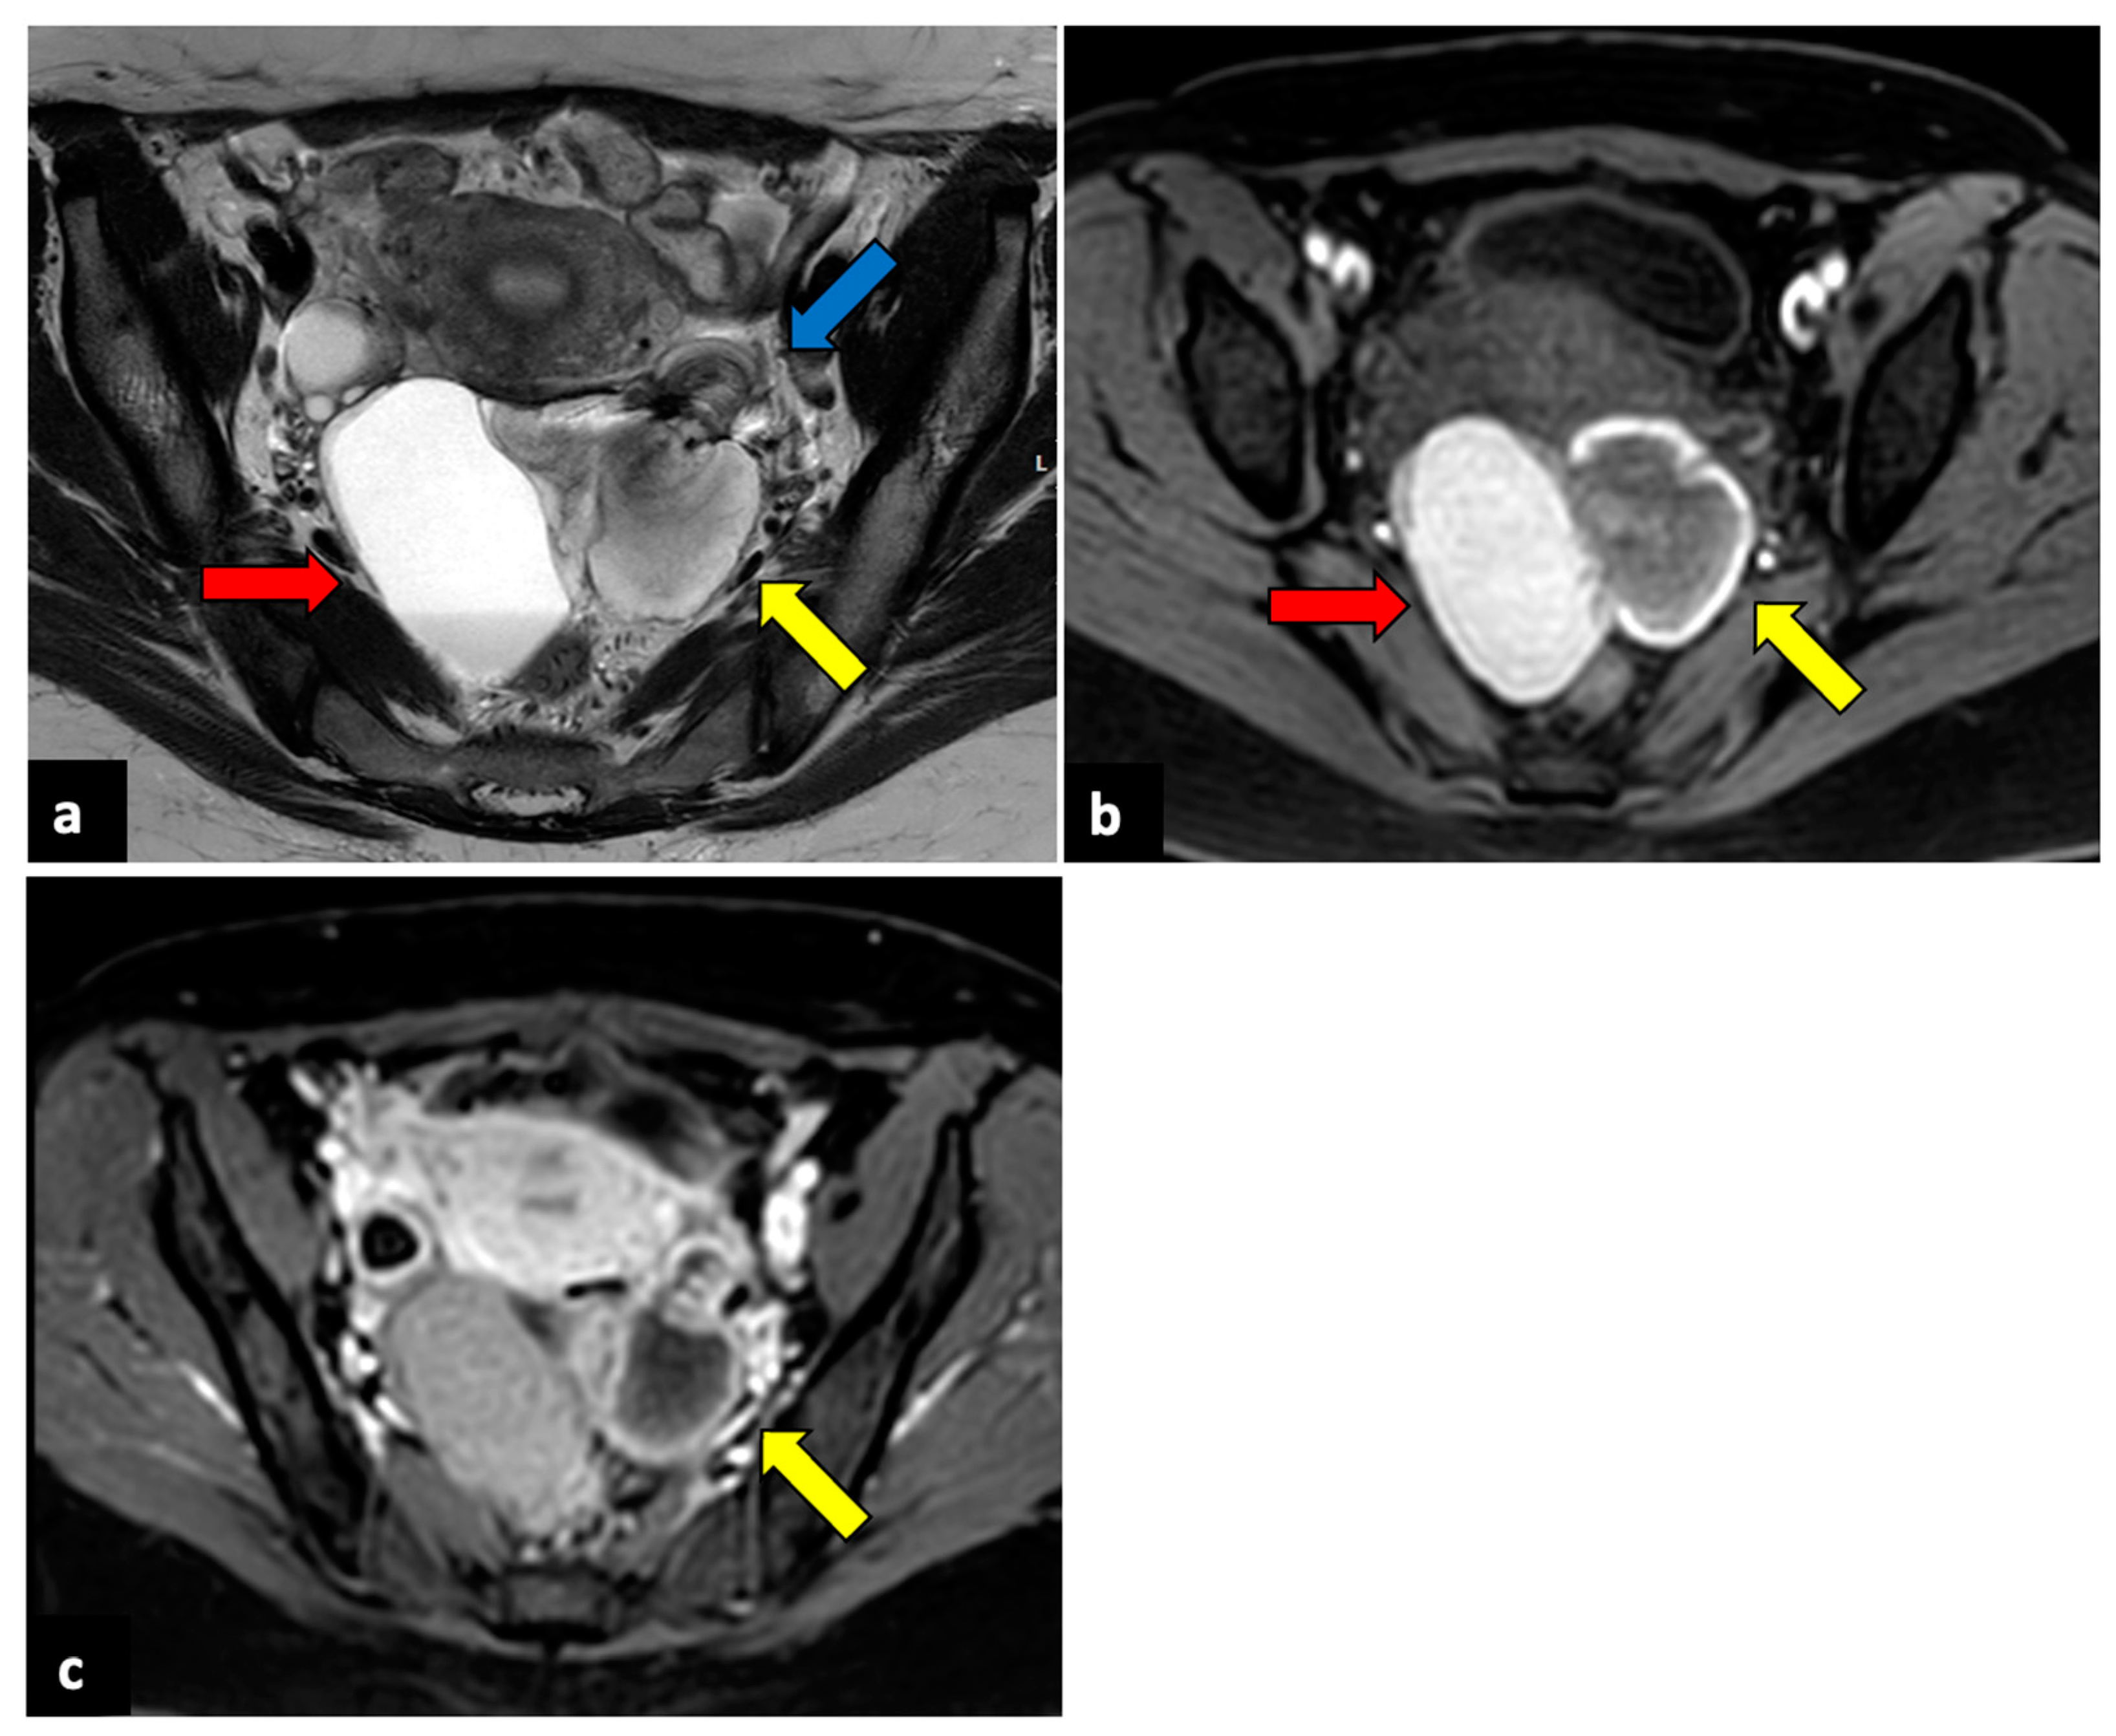

2.3. Pelvic Inflammatory Disease

2.4. Complicated Uterine Leiomyomas